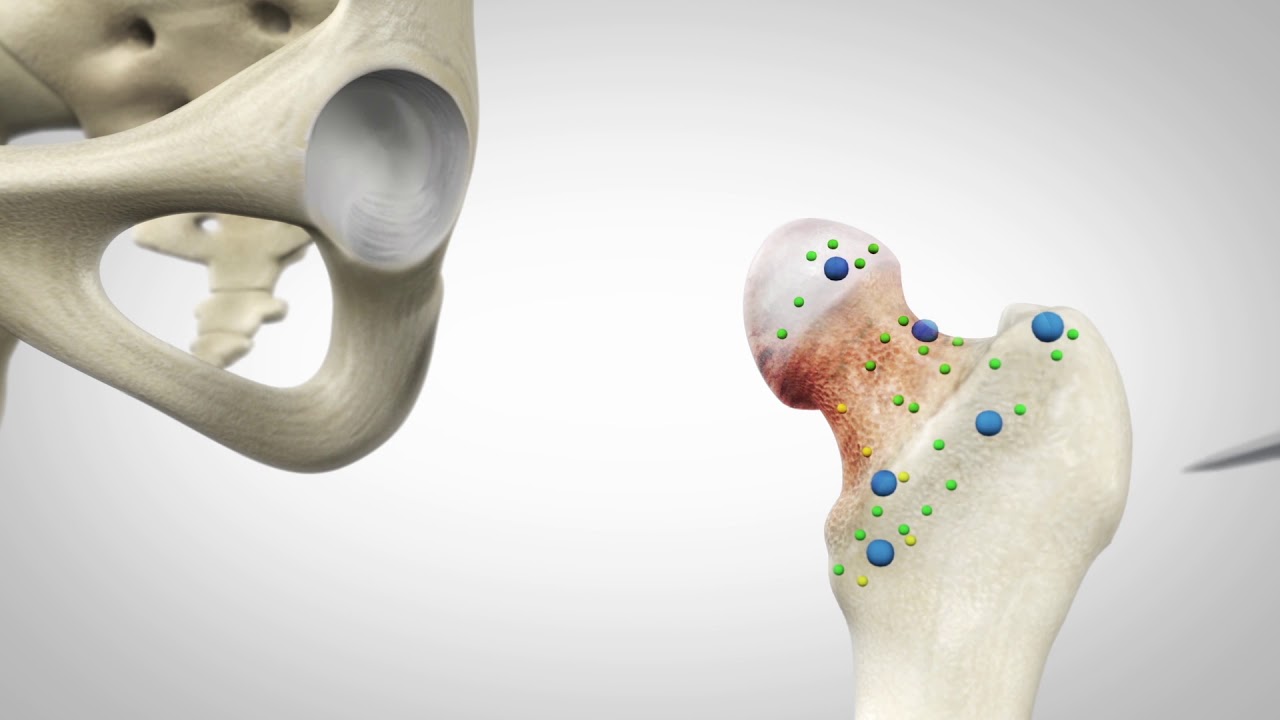

Robotic-Arm Assisted THA in Developmental Hip Dysplasia

Mako robotic arm assisted surgery – Total Hip Replacement